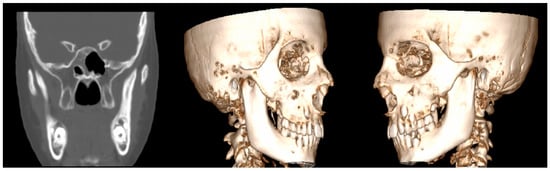

- Case 5

| 5 | Female | 45 | External auditory canal abscess |

OPG CT/MRI | 10 mm | Incision and drainage of the abscess | 51 mm |